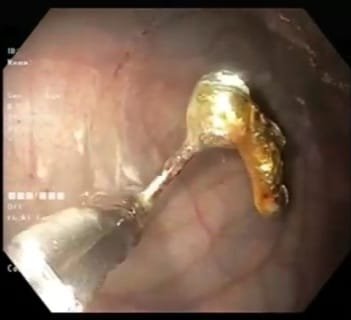

ERCP (Endoscopic Retrograde Cholangiopancreatography) is a specialized procedure used to diagnose and treat conditions affecting the bile ducts, gallbladder, and pancreas. Problems such as bile duct stones, blockages, strictures, and recurrent jaundice often require ERCP for accurate diagnosis and effective relief.

At Sapphire Gastroenterology Center, ERCP is performed with advanced technology to safely remove stones, relieve obstructions, and place stents when needed. This helps reduce pain, prevent infections, and avoid major surgery in many cases. Early ERCP intervention can prevent serious complications such as cholangitis, pancreatitis, and long-term liver damage.